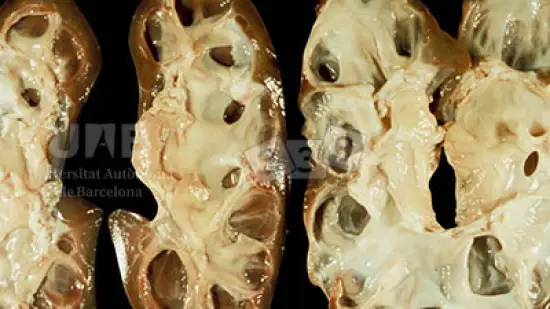

Semana de 07-Dez-2022

Onde estão localizados estes quistos?